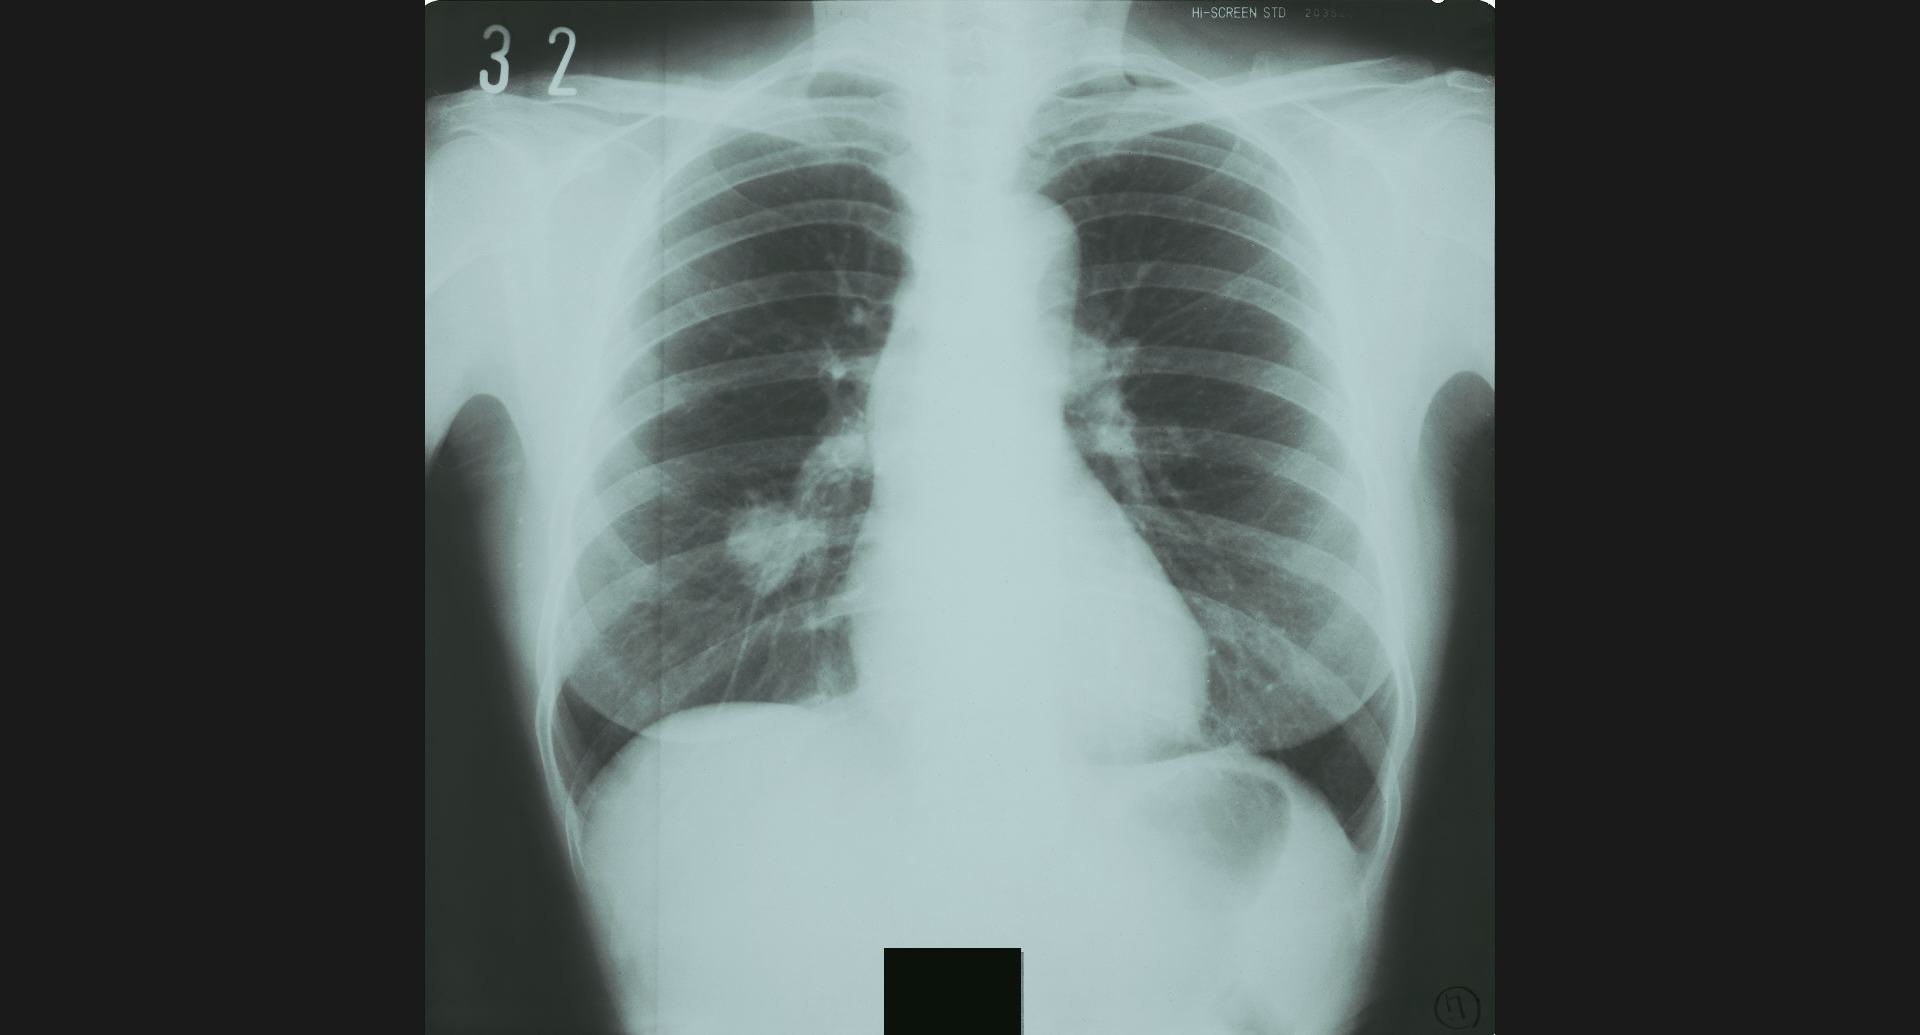

fig.1(117KB) :Alveolar microlithiasis

細かい肺病変、air bronchogram。